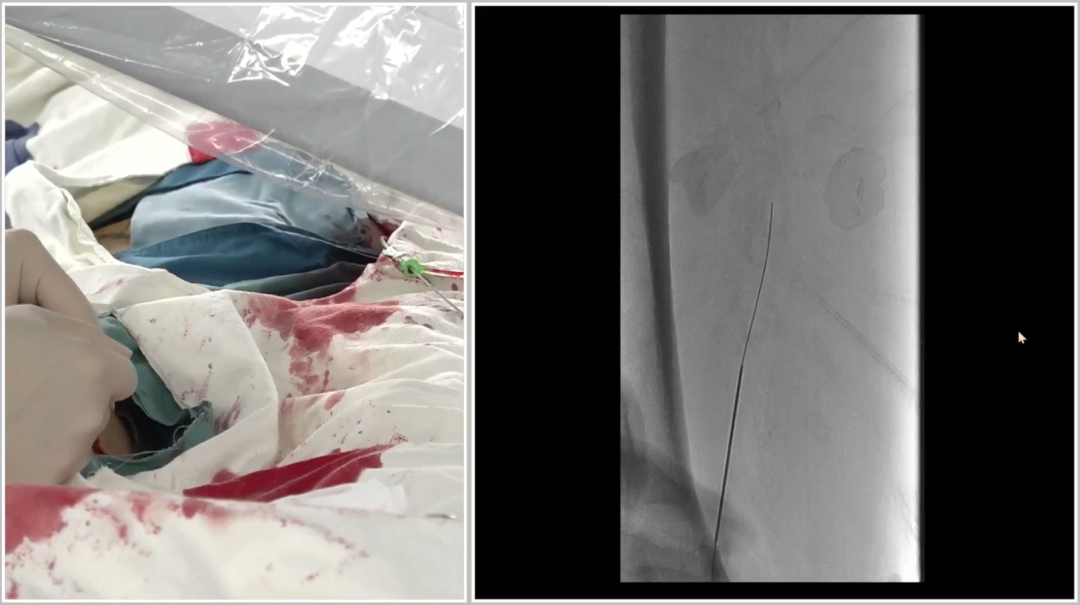

跟进V18导丝突破远端纤维帽,配合支撑导管完成对接。

逆穿的难点在于选择合适的对接位置,对接判断要点是导丝成袢后,通过近端Terumo导丝触碰,若有明显"碰触感",提示位于同一内膜下,可确认对接。